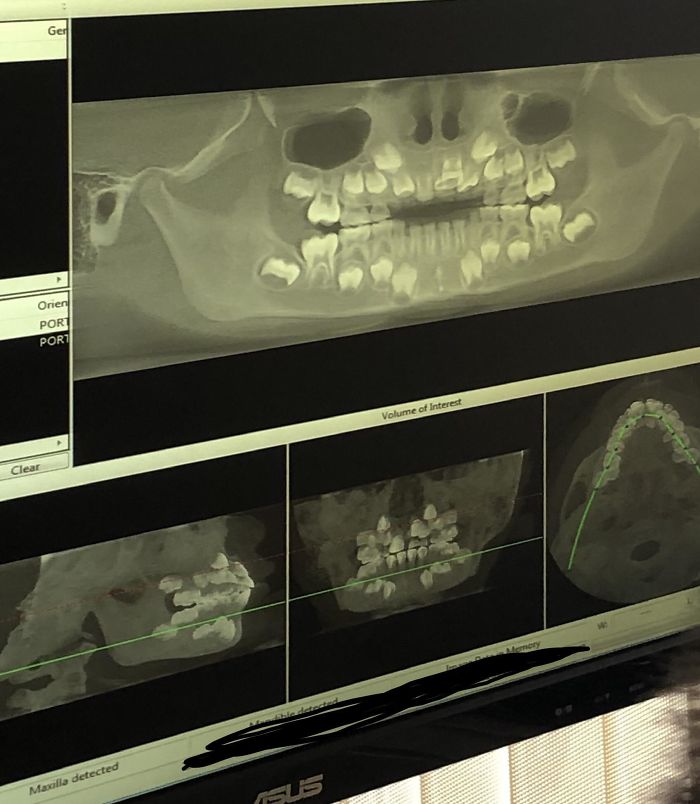

Dental 3D X-Ray On A Child

X-Rays Of Children's' Mouths Between The Ages Of 6-12 Years Still Hold Wonder For Me, Even After Being A Dentist For 10+ Years

I Have A Rare Disorder Called Cleidocranial Dysotosis. Got My First Dental X-Ray Today And I Have A Lot Of Extra Teeth